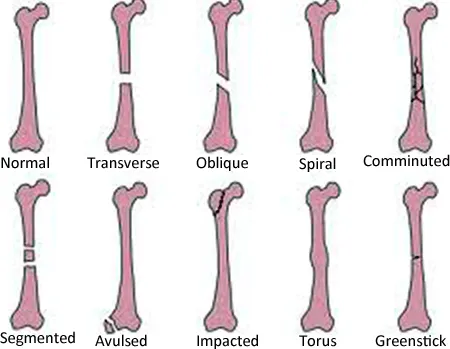

explain the Classification of fracture.( ફ્રેક્ચરનું ક્લાસિફિકેશન વણૅવો).

1) કમ્પલીટ ફ્રેક્ચર

આમાં બોન એ ક્રોસ સેક્શનમાં બ્રેક ડાઉન થાય છે.કમ્પ્લીટ ફ્રેક્ચરમાં બોન એ બે પાર્ટસમાં ડિવાઇડ થાય છે.

2)ઇનકમ્પલીટ ફ્રેક્ચર

આમા બોન એ કમ્પ્લીટલી બ્રેક ડાઉન થતું નથી.ઇનકમ્પ્લીટ ફ્રેક્ચરમાં બોન એક ક્રેક થાય છે પરંતુ કંપલીટલી બ્રેકડાઉન થતું નથી.

3)ક્લોઝ્ડ ફ્રેક્ચર

ક્લોઝ ફેક્ચર ને સિમ્પલ ફ્રેક્ચર પણ કહેવામાં આવે છે.આમાં બોન એ બેકગ્રાઉન્ડ થાય છે.

પરંતુ તે સ્કિન ની અંદર જ રહે છે એટલે કે સ્કીન એ ઇન્ટેકટ હોય છે જેથી વુંડ એ ઓપન હોતો નથી કે દેખાતો નથી તથા ફ્રેક્ચર સાઈડ એ સ્કિન એ ઇંટેક્ટ હોય છે.

4)ઓપન ફ્રેક્ચર

ઓપન ફ્રેક્ચર ને કમ્પાઉન્ડ ફ્રેક્ચર પણ કહેવામાં આવે છે.આમાં બોન એ સ્કીન ઉપરથી બ્રેક ડાઉન થઈ બહાર વિઝીબલ હોય છે.

ફ્રેક્ચર સાઇટ એ ઇન્ટરપટેડ સ્કીન હોય છે.

ઓપન ફ્રેકચર હોય તો બેક્ટેરિયા તે ઓપન સાઇટમાંથી એન્ટર થઈ અને ઇન્ફેક્શન ક્રિએટ કરે છે.

એકોર્ડિગ ટુ ગ્રેડ

ગ્રેડ 1

આમાં વુંડ એ કલિયર હોય છે તથા એક સેન્ટિમીટર કરતાં નાનું હોય છે.

ગ્રેડ 2

આમાં વુંડ એ મોડેરેટ અમાઉન્ટમાં હોય છે તથા એક સેન્ટિમીટર મોટું હોય છે.

ગ્રેડ 3

આમા વુંડ એ ખૂબ જ હાઇલી કંટામિનેટેડ હોય છે સાથે તેમાં વધુ પ્રમાણમાં સોફ્ટ ટિશ્યૂ, નર્વે, તથા ટેન્ડન નુ ઇન્વોલ્વમેન્ટ હોય છે અને વુંડ એ 6-8 cm કરતા મોટું હોય છે.

5) ડીસપ્લેસડ ફ્રેક્ચર

આ ફેક્ચર એ એવા પ્રકારનું છે કે જેમાં બ્રેક થયેલા બોન એ ના એન્ડ એ એકબીજાથી સેપરેટ થાય છે અને આ મુખ્યત્વે પડી જવાના કારણે જોવા મળે છે.

6)કોમ્યુનિટેડ ફ્રેક્ચર

આમાં બોનફ્રેગ્મેન્ટ એ ક્રશ તથા ઘણા બધા ભાગમાં બ્રેક ડાઉન થાય છે.

આમાં મુખ્યત્વે જે એલ્ડરલી પીપલ હોય તેના ફોલ ડાઉન થવાના કારણે જોવા મળે છે.

ક્લાસિફિકેશન બાય ફ્રેક્ચર પેટર્ન

1)લિનિયર ફ્રેક્ચર

આમાં ફ્રેક્ચર એ બોન ના લોંગ એક્સિસના પેરેલલ હોય છે.અને આ મુખ્યત્વે બોન ઉપર ડાયરેકટ ફોર્સ લાગવાના કારણે જોવા મળે છે.

2) ટ્રાન્સવર્ઝ ફ્રેક્ચર

આમાં ફ્રેક્ચર એ 90 ડિગ્રીએ જોવા મળે છે.

Ex:= paget ‘s disease,

Osteomalacia.

3)ઓબ્લિક ફ્રેક્ચર

આમાં fracture એ 45° ડિગ્રી ના ખૂણે જોવા મળે છે.આફ્રેક્ચર એ મુખ્યત્વે ટિવસ્ટીંગ ફોર્સ લાગવાના કારણે જોવા મળે છે.

4) સ્પાઇરલ ફ્રેક્ચર

સ્પાઇરલ ફ્રેક્ચર ને ટોરસન ફ્રેક્ચર કહેવામાં આવે છે. આ બોનફેક્ચર કહેવામાં આવે છે.

આ મુખ્યત્વે ટ્વીસ્ટીંગ ફોર્સ લાગવાના કારણે જોવા મળે છે.

5)ડિપ્રેસ્ડ ફ્રેક્ચર

આ ફેક્ચર એ મુખ્યત્વે સ્કલ બોન તથા ફેશિયલ માં ડિપ્રેસ થવાના કારણે જોવા મળે છે.

6)લોન્જીટ્યુડિનલ ફ્રેક્ચર

એ મુખ્યત્વે એવું ફ્રેક્ચર છે કે જે બોનના લોંગ એકસીસમાં જોવા મળે છે.

આમાં ફેક્ચર લાઇન એ લોન્જીટ્યુડિનલી હોય છે.

ક્લાસિફિકેશન બાય ટાઇપ ઓફ ફ્રેક્ચર

1)એવલ્સન ફ્રેક્ચર

આ એવું ફ્રેક્ચર છે કે જેમાં બોનનો સેગમેન્ટ એ લીગામેન્ટ તથા ટેંડન માંથી બ્રેક ડાઉન થાય છે.

2)કંપ્રેસન ફ્રેક્ચર

કમ્પ્રેસન ફ્રેક્ચરને ક્રસ ફ્રેક્ચર પણ કહેવામાં આવે છે.અને આ મુખ્યત્વે કોઇપણ કમ્પ્રેશન એબોનમાં લાગવાના કારણે જોવા મળે છે.

3)ગ્રીન સ્ટિક ફ્રેક્ચર

આમાં એક બાજુના પાર્ટમાંથી બોન એ બ્રેકડાઉન થાય છે અને બીજી બાજુએ બોન એ બેન્ડ વળી જાય છે.

4) ઇમ્પેક્ટ ફ્રેક્ચર

ઇમ્પેક્ટેડ ફ્રેક્ચર માં બોનની કંટીન્યુટી એ લોસ થાય છે.

5)પેથોલોજિકલ ફ્રેક્ચર

આ ફ્રેક્ચર એ મુખ્યત્વે જ્યારે કોઇ ડીઝીસ્ટ બોન હોય ત્યાંથી બ્રેકડાઉન થાય છે અને ફ્રેક્ચર જોવા મળે છે.

6) સ્ટ્રેસ ફ્રેક્ચર

સ્ટ્રેસ ફ્રેક્ચર એ વારંવાર બોન ઉપર લોડિંગ આવવાના કારણે જોવા મળે છે.